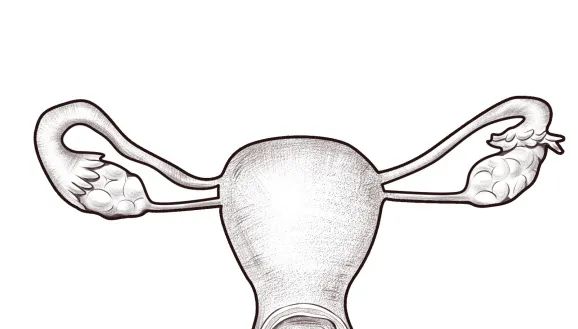

正常的子宫腔是一个类似倒三角或者倒梨形,宫腔也是空空的,是个宽敞的一室户。虽然宫腔有大小之分,但是正常情况下,并不影响生育。

这么说吧,本来的一室户,突然建一堵墙,变成了两室户,每个房间的面积是不是就小了很多?

一个宫腔被纵膈分成两个

这在医学上叫子宫纵膈,属于最常见的子宫腔畸形,就是在宫腔的中间多出了一道隔(墙),而且这面墙的长度不一(分为完全纵隔与不全纵隔),厚度也不一样。这一面“墙壁”的存在可能使得子宫腔变狭小。

比如佳佳,而从核磁结果上看,子宫就变成了一个Y形,左右两边的宫腔都太小了。